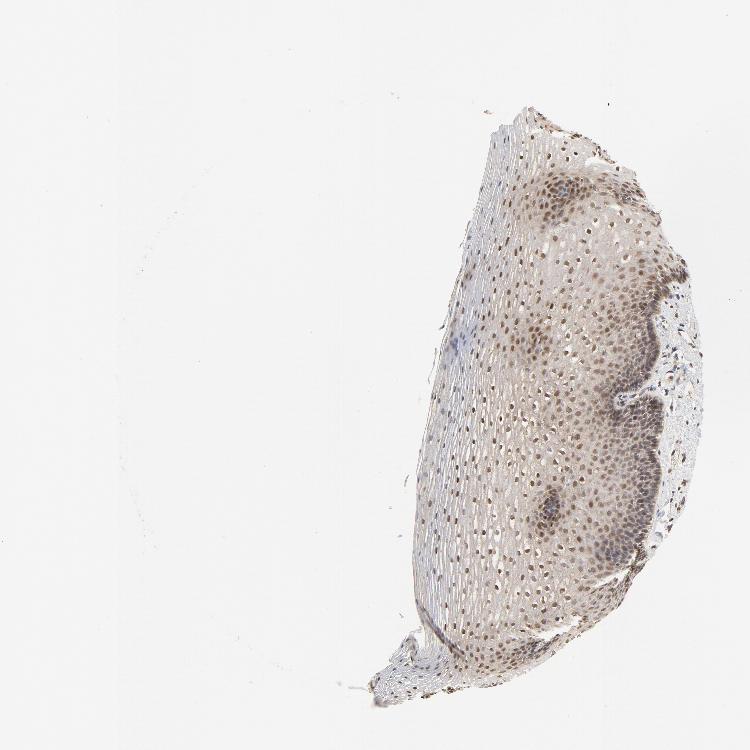

ESOPHAGUS - Antibody stainingi

Antibody staining in the annotated cell types in the current human tissue is reported as not detected, low, medium, or high, based on conventional immunohistochemistry profiling in selected tissues. This score is based on the combination of the staining intensity and fraction of stained cells.

Each image is clickable and will lead to virtual microscopy that enables deeper exploration of all samples and also displays staining intensity scores, fraction scores and subcellular localization as well as patient and tissue information for each sample.

Antibody CAB004082

Squamous epithelial cells Medium